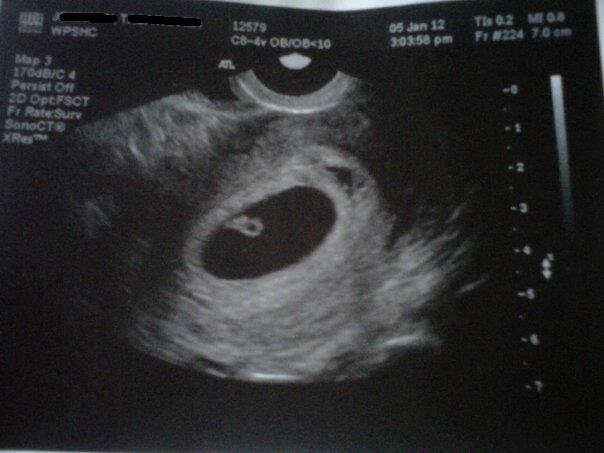

6w6d ultrasound (transvaginal) left of photo = my right (right of photo = my left)

Attachment 1934